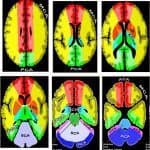

Giải Phẫu Tưới Máu Não | Bài giảng CĐHA

Hình ảnh giải phẫu tưới máu não.